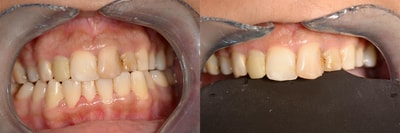

Esthétique du sourire DSD

Certains cas nécessitent une analyse de l’Esthétique du Sourire. Après une prise d’empreinte, l’appréciation de certaines mesures et la prise de clichés photographiques, nous étudierons la cohérence de votre sourire par rapport à certaines références, et vous proposerons, lorsque c’est nécessaire, une étude de votre cas. Elle sera accompagnée d’un projet esthétique virtuel.

Si ce projet est validé, nous validerons un essai (masque esthétique en bouche). En cas de validation, nous pourrons entamer les travaux esthétiques.

Cas numero 1 :

Situation Initiale

Etude du cas et proposition

Cas terminé

Cas numero 2 :